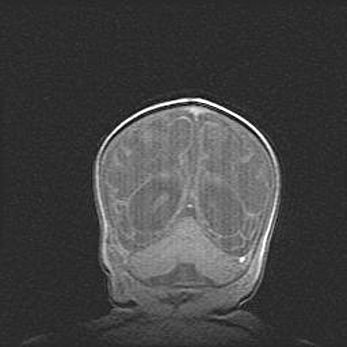

Лейкомаляция с кистозно-глиозной дегенерацией головного мозга.

Возраст: 2 месяца 25 дней

Вес: 6400 г

Окружность головы: 40 см

Срок гестации: 41 неделя

Лейкомаляцию относят к ишемически-гипоксическим повреждениям головного мозга, диагностируемым у новорожденных. При лейкомаляции в головном мозге обнаруживают очаги некроза, возникшие после тяжелой гипоксии и нарушения кровотока. В процессе морфогенеза очаги проходят три стадии: 1) развития некроза, 2) резорбции и 3) формирования глиозного рубца или кисты. Перивентрикулярная лейкомаляция (ПЛ) встречается примерно в 12% случаев среди новорожденных, обычно – у недоношенных детей, причем, частота ее зависит от массы, с которой младенец появился на свет. Наибольшее число малышей страдает лейкомаляцией, если масса при рождении 1500-2500 г.